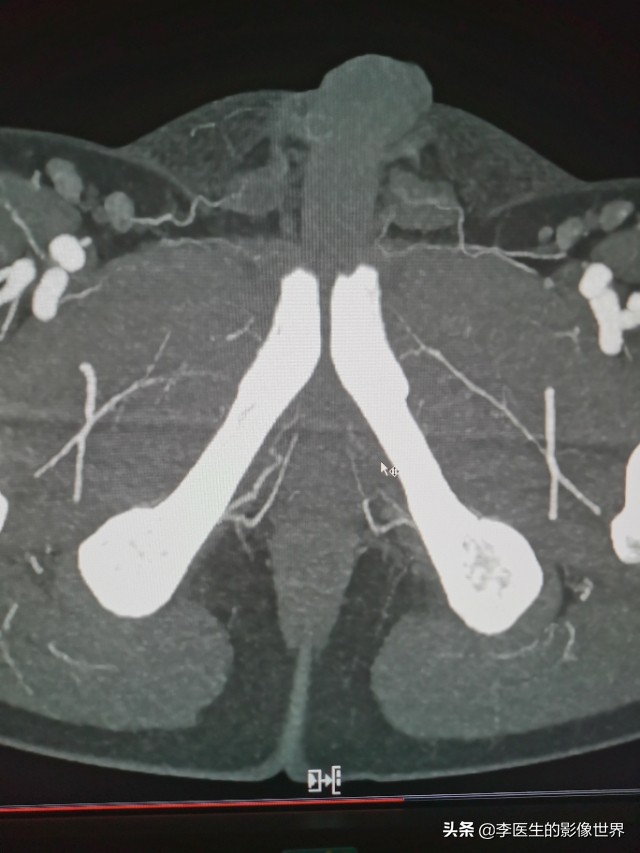

CT血管成像作为一种无创检查,能够作为数字血管造影(DSA)的有效补充,初步判断血管解剖结构异常、血管狭窄、外伤等。

为临床诊断、手术方案制定提供便利。以下为阴部内动脉CT血管成像MIP、VR图。仅供交流。

右侧阴部内动脉显示清晰,分出YJ动脉、会阴动脉。

鼠标所指左侧YJ动脉狭窄、显示不清。